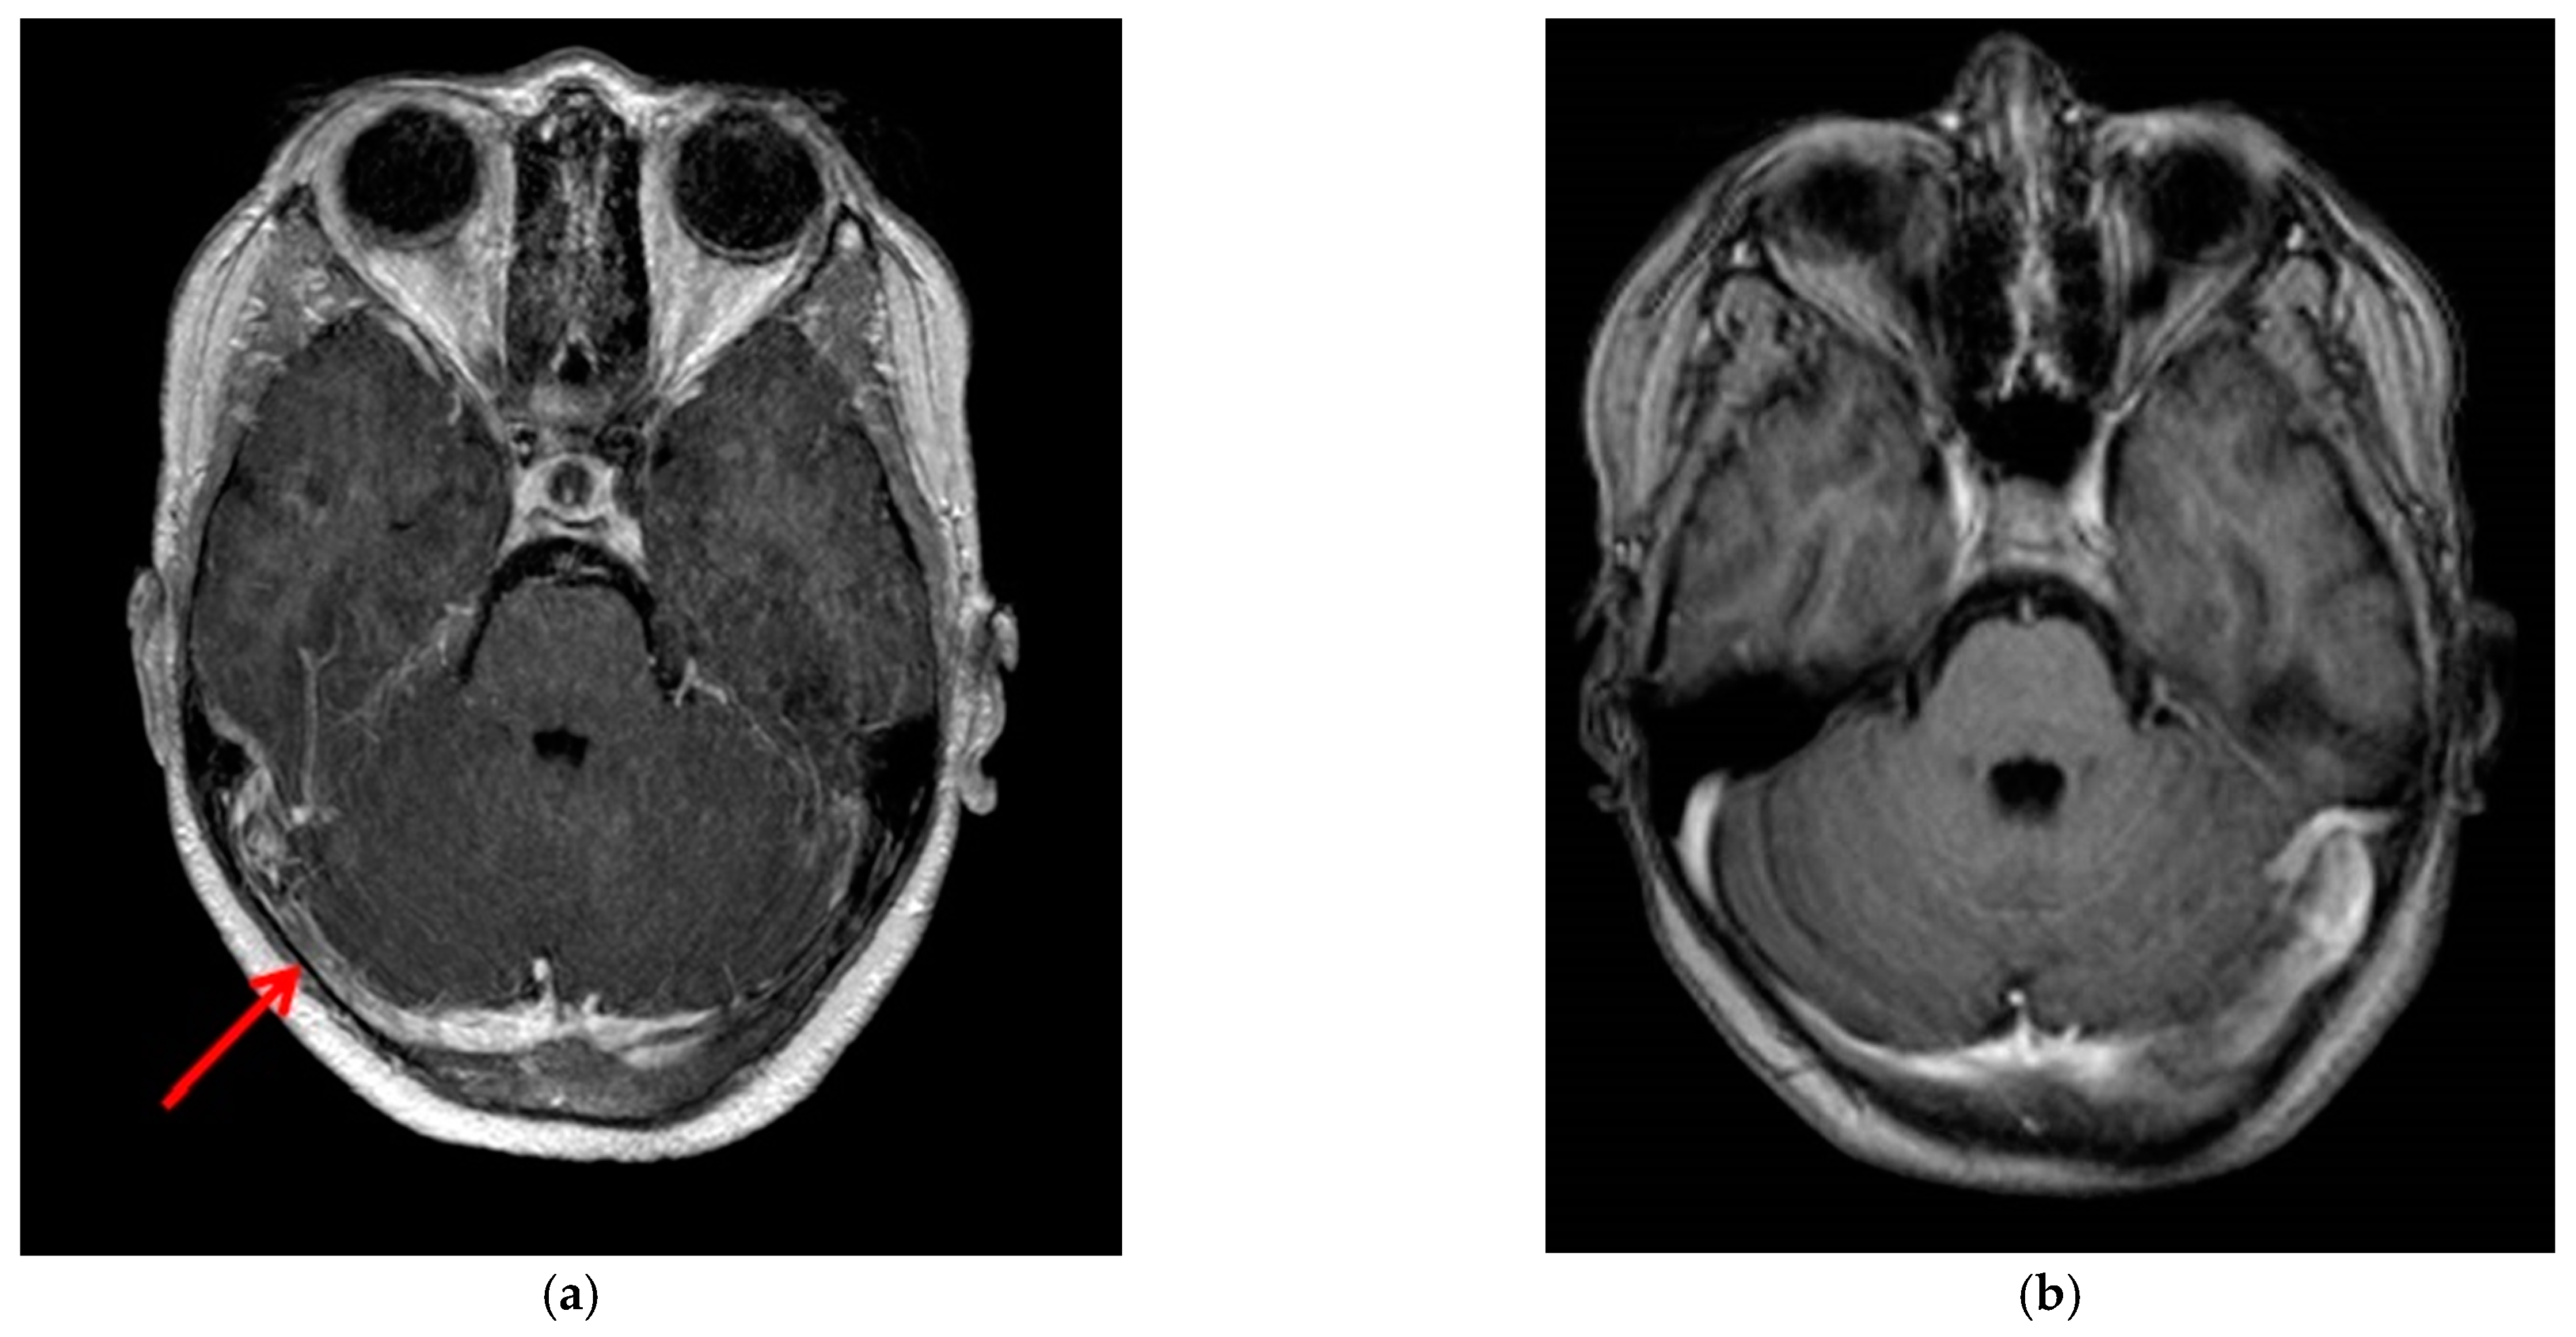

2. Case Presentation